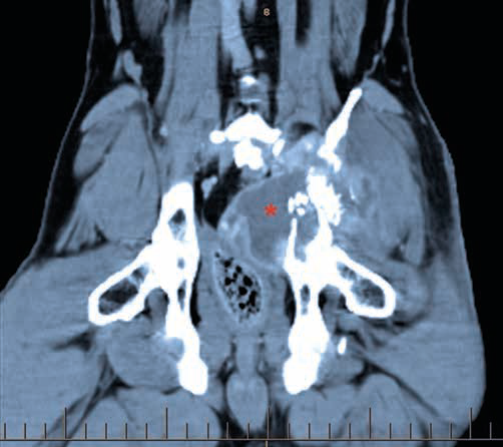

Ectopic Ureters – Marty’s rare condition Marty, an adorable golden retriever puppy, was just 15 weeks old when he first presented to the VSA team in Sylvia Park. He presented initially to the medicine department for urinary incontinence which was …